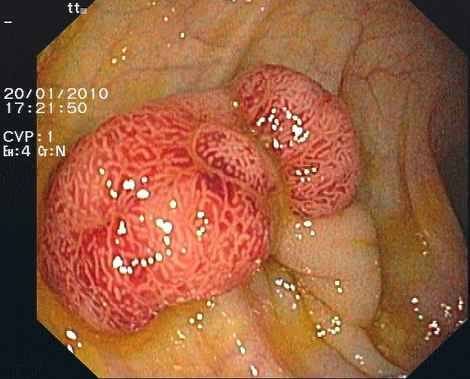

Wenn bei der Darmspiegelung Polypen gefunden werden, können diese in aller Regel während des Eingriffs entfernt werden (Polypektomie). Es handelt sich meist um Adenome, von Drüsengewebe des Dickdarms ausgehende Tumoren. Aus diesen - eigentlich gutartigen - Läsionen können sich innerhalb von Jahren bösartige Tumoren (Dickdarmkrebs) entwickeln. Die Vorsorgekoloskopie und Polypektomie können effektiv Darmkrebs verhindern.

Zur Abtragung gestielter Polypen wird eine Drahtschlinge über das Endoskop eingeführt und um den Stiel gelegt. Dann wird diese zugezogen und der Polyp wird mit hochfrequentem Strom abgeschnitten. Durch die Hitze, die dabei entsteht, werden Gefäße verschlossen, so dass meist keine relevante Blutung auftritt.

Viele Polypen sind flach und damit mit der Schlinge nicht so gut zu fassen. Bei solchen Polypen ist eine Chromoendoskopie mit Indigokarmin hilfreich, um sie besser abgrenzen zu können. Dann wird mit einer Injektionsnadel, die auch durch das Endoskop eingeführt wird etwas verdünnte Adrenalinlösung in die Schleimhaut unter dem Polypen injiziert. Der Polyp hebt sich halbkugelig ab und kann mit der Schlinge gefasst und abgeschnitten werden. Durch das Adrenalin verengen sich die Gefäße des Polypen, so dass eine Blutung verhindert wird.

Kommt es dennoch zu einer Blutung, kann diese fast immer mittels Klammern, die auf die blutende Stelle gesetzt werden (Clips), gestillt werden. Der Polyp wird mit einer Zange oder der Schlinge gefasst und zusammen mit dem Endoskop herausgezogen.

Die Polypektomie ist für Sie schmerzlos, kann aber etwas länger dauern als eine diagnostische Koloskopie. Wenn mehrere Polypen vorhanden sind, sind manchmal mehrere Sitzungen notwendig. Selten findet man sehr große Polypen, bei denen nach Abtragung eine stationäre Überwachung im Krankenhaus notwendig ist.